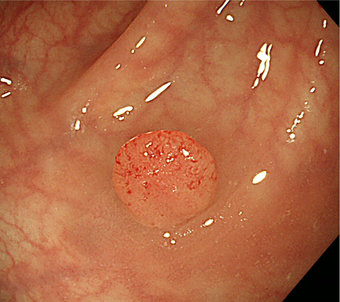

図 大腸がん

図 大腸ポリープ

肛門から大腸に内視鏡を挿入して大腸内を直接調べる検査です。大腸内に便が残っていると十分な観察ができません。前日から食事制限が必要で、検査当日には腸管洗浄液を1〜2リットル飲み、腸管内をきれいにしてから検査を行います。通常検査は10-20分程ですが、検査には多少の苦痛を伴うため、当院では希望される方には鎮静剤を使用して検査を行っています。大腸内視鏡検査では、大腸がんや大腸ポリープを見つけることができます。